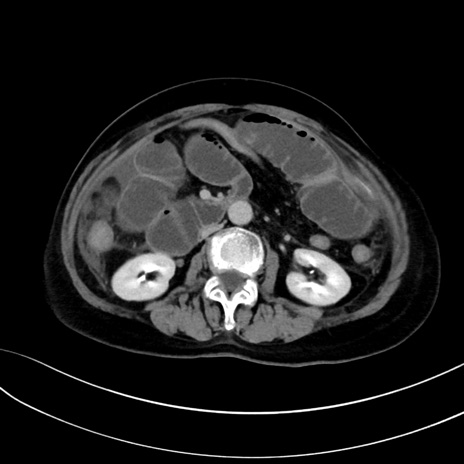

症例13 CT(横断像)1日半後

(冠状断像)1日半後